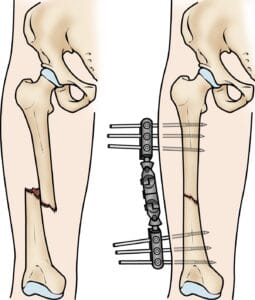

Intramedullary nailing is currently the preferred method for treating femoral shaft fractures. This procedure involves inserting a specially designed metal rod, or nail, into the femur’s canal. The nail spans the fracture site, stabilizing the bone and promoting proper alignment during healing.

The intramedullary nail can be inserted at either the hip or knee end of the femur. Screws positioned above and below the fracture maintain proper alignment as the bone heals. Intramedullary nails are typically made of titanium and come in various sizes to fit different femur dimensions.

Intramedullary nailing provides strong, stable, full-length fixation.

Plates and Screws

In some situations, such as when a fracture extends into the hip or knee joint, intramedullary nailing may not be an option. Instead, the fractured bone fragments are realigned (reduced) and secured using screws and metal plates placed along the outer bone surface. This method effectively stabilizes complex fractures, particularly near joint areas.

(Left) This X-ray, taken from the side, shows a transverse fracture of the femur. (Right) In this front view X-ray, the fracture has been treated with intramedullary nailing.